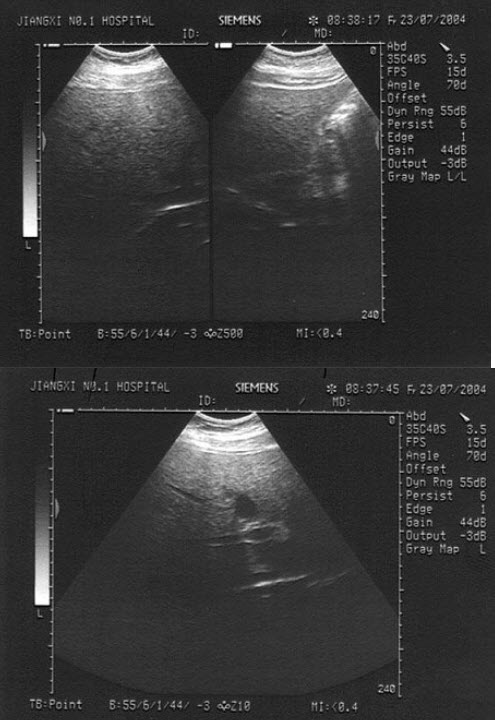

10、单项选择题

女,40岁,有时右上腹隐痛2年余。结合超声声像图,最可能的诊断为()

A.肝血管瘤

B.肝脓肿

C.小肝癌

D.转移性肝癌

E.肝囊肿